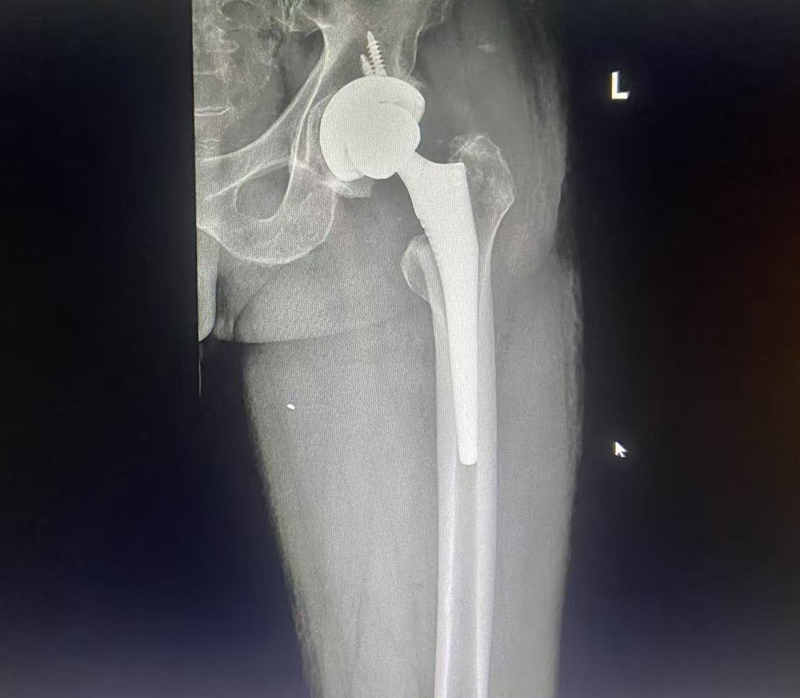

在排除手术禁忌症后,于11月7日李李连亭主任亲自为患者施行左侧全髋关节置换术。整个手术过程顺利,术中出血量少,患者术后恢复迅速。

术后第五天的康复评估中,患者已能够不依靠助行器独自行走,且步态平稳。这一显著的康复效果,超出了医疗团队的预期,也为患者今后的生活质量带来了极大的改善。